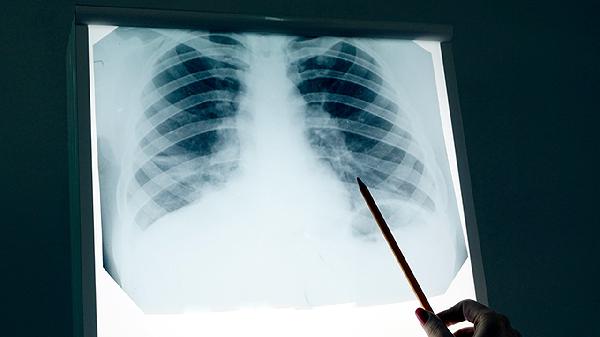

肿瘤与气管的毗邻关系是手术关键。若肿瘤仅压迫气管但未侵犯管壁,通常可完整切除;若已浸润气管软骨或黏膜层,需联合气管袖状切除术。术前需通过支气管镜和三维重建CT明确浸润深度。

根据肿瘤位置选择肺叶切除+气管成形术或全肺切除术。达芬奇机器人手术可提高气管吻合精度,对紧贴气管的肿瘤,术中需联合快速病理确认切缘阴性。